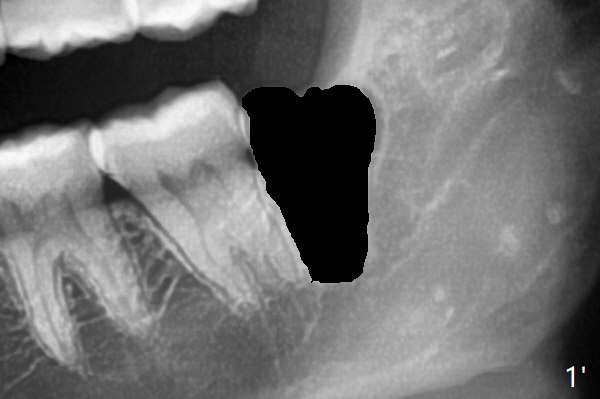

7和8之间只有一层骨皮质(图一:>),8拔除后(图一’),7远中骨质可能退缩,所以植骨尤其重要。医用石膏(Bond Apatite,图二),表面放置1/2胶原塞,4-0 PGA缝合。